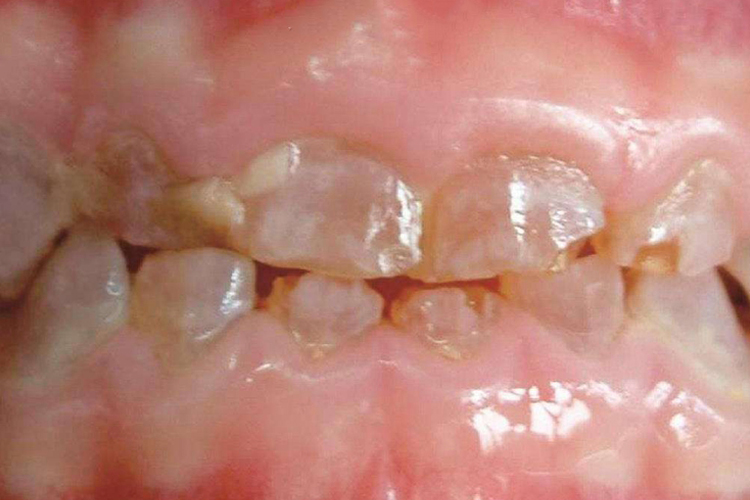

遗传性乳光牙应指遗传性乳光牙本质,也为牙本质发育不全Ⅱ型。乳牙和恒牙皆可发生,常为全口牙齿受侵犯。牙齿呈半透明的(乳光的)黄褐色,釉质早期与牙本质分离而剥落,牙本质暴露,使颜色更深,呈棕紫色,而且易磨损。X线片可见牙根短而细,牙髓腔缩小,甚至完全闭塞。

遗传性乳光牙本质一般用修复的方法恢复牙列,由于乳牙列常有严重咀嚼磨损,故需用覆盖(牙合)面和切缘的(牙合)垫预防和处理。在恒牙列,为防止过度的磨损,可用全冠,也可用(牙合)垫进行修复。